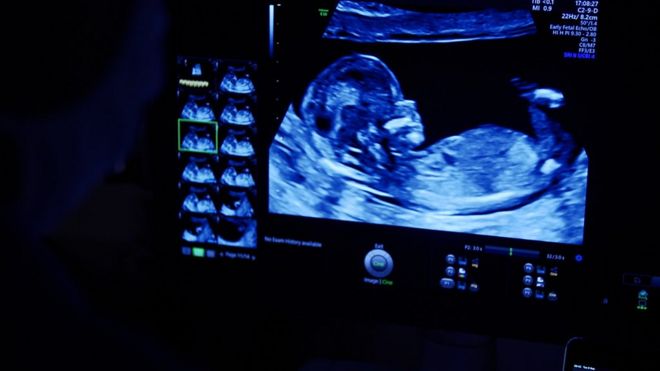

Our affordable early viability private pregnancy scan / 6 week / dating scan is designed to provide you with reassurance in the early stages of your first trimester . We will assess the viability of the pregnancy i .e . visualise fetal heartbeat, assess ectopic pregnancy, vaginal bleeding or pelvic pains & determine if single or multiple pregnancy .

A probe placed on the body emits sound waves into the body, listens for the return echo and generates an image . 4D ultrasound will be similar therefore to a conventional scan in terms of exposure . This is likely the same machine that the NHS will use in your 12 week dating and 20 week anomaly scans .